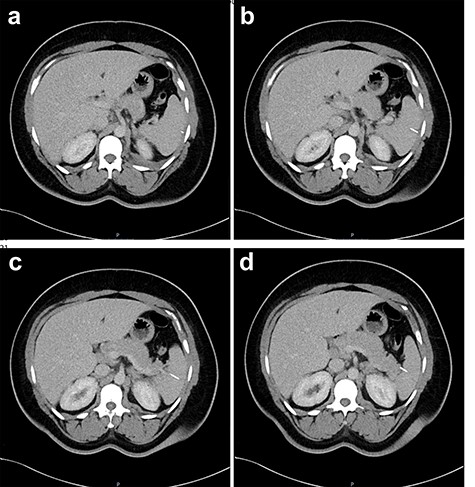

Contact with the previous hospital that treated the patient for her empyema revealed the splenic foreign body pre-dated any hospital admission or intervention; the empyema fluid culture had grown Staphylococcus aureus and S. anginosus, and that there was no splenic collection on CT before the VATS procedure (Fig. 4). The patient had no previous hospital admissions, operations or other exposure to needles; the GP confirmed that there was no past psychiatric history. The patient had moved to the UK from Grenada, Caribbean aged 7 and that she was not aware of any procedures prior to this age.

Two-mm axial sections from a CT scan in January 2020, performed after the VATS procedure, to check resolution of the empyema that shows the foreign body impacted in the spleen without evidence of haematoma. (a) section number 18, (b) section number 19, (c) section number 20, (d) section number 21.